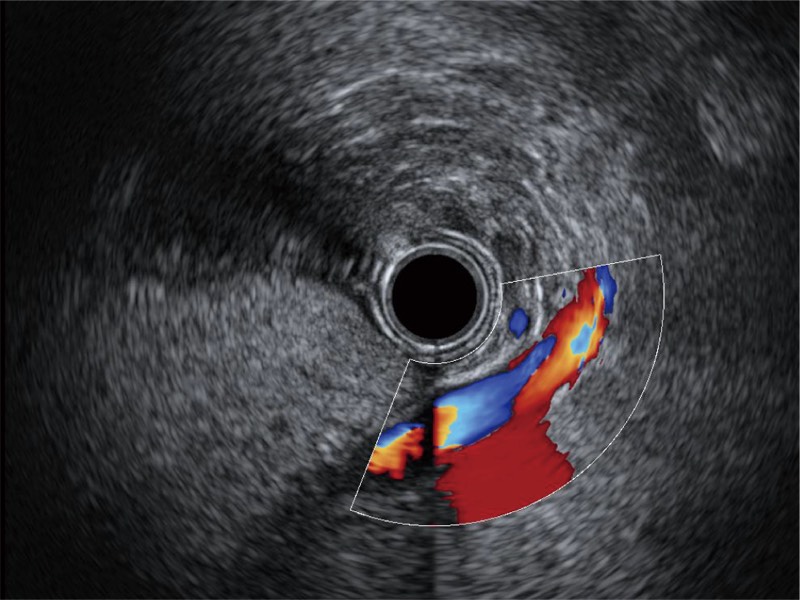

• 清晰显示胆总管及周围血管分布

EG-UR5

超声电子上消化道内窥镜